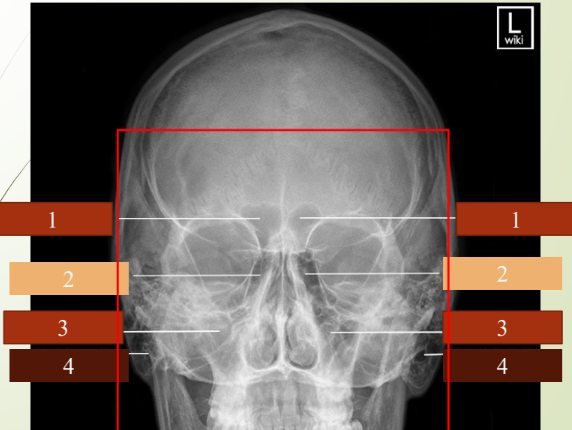

Paranasal sinuses visual

knowt flashcard image